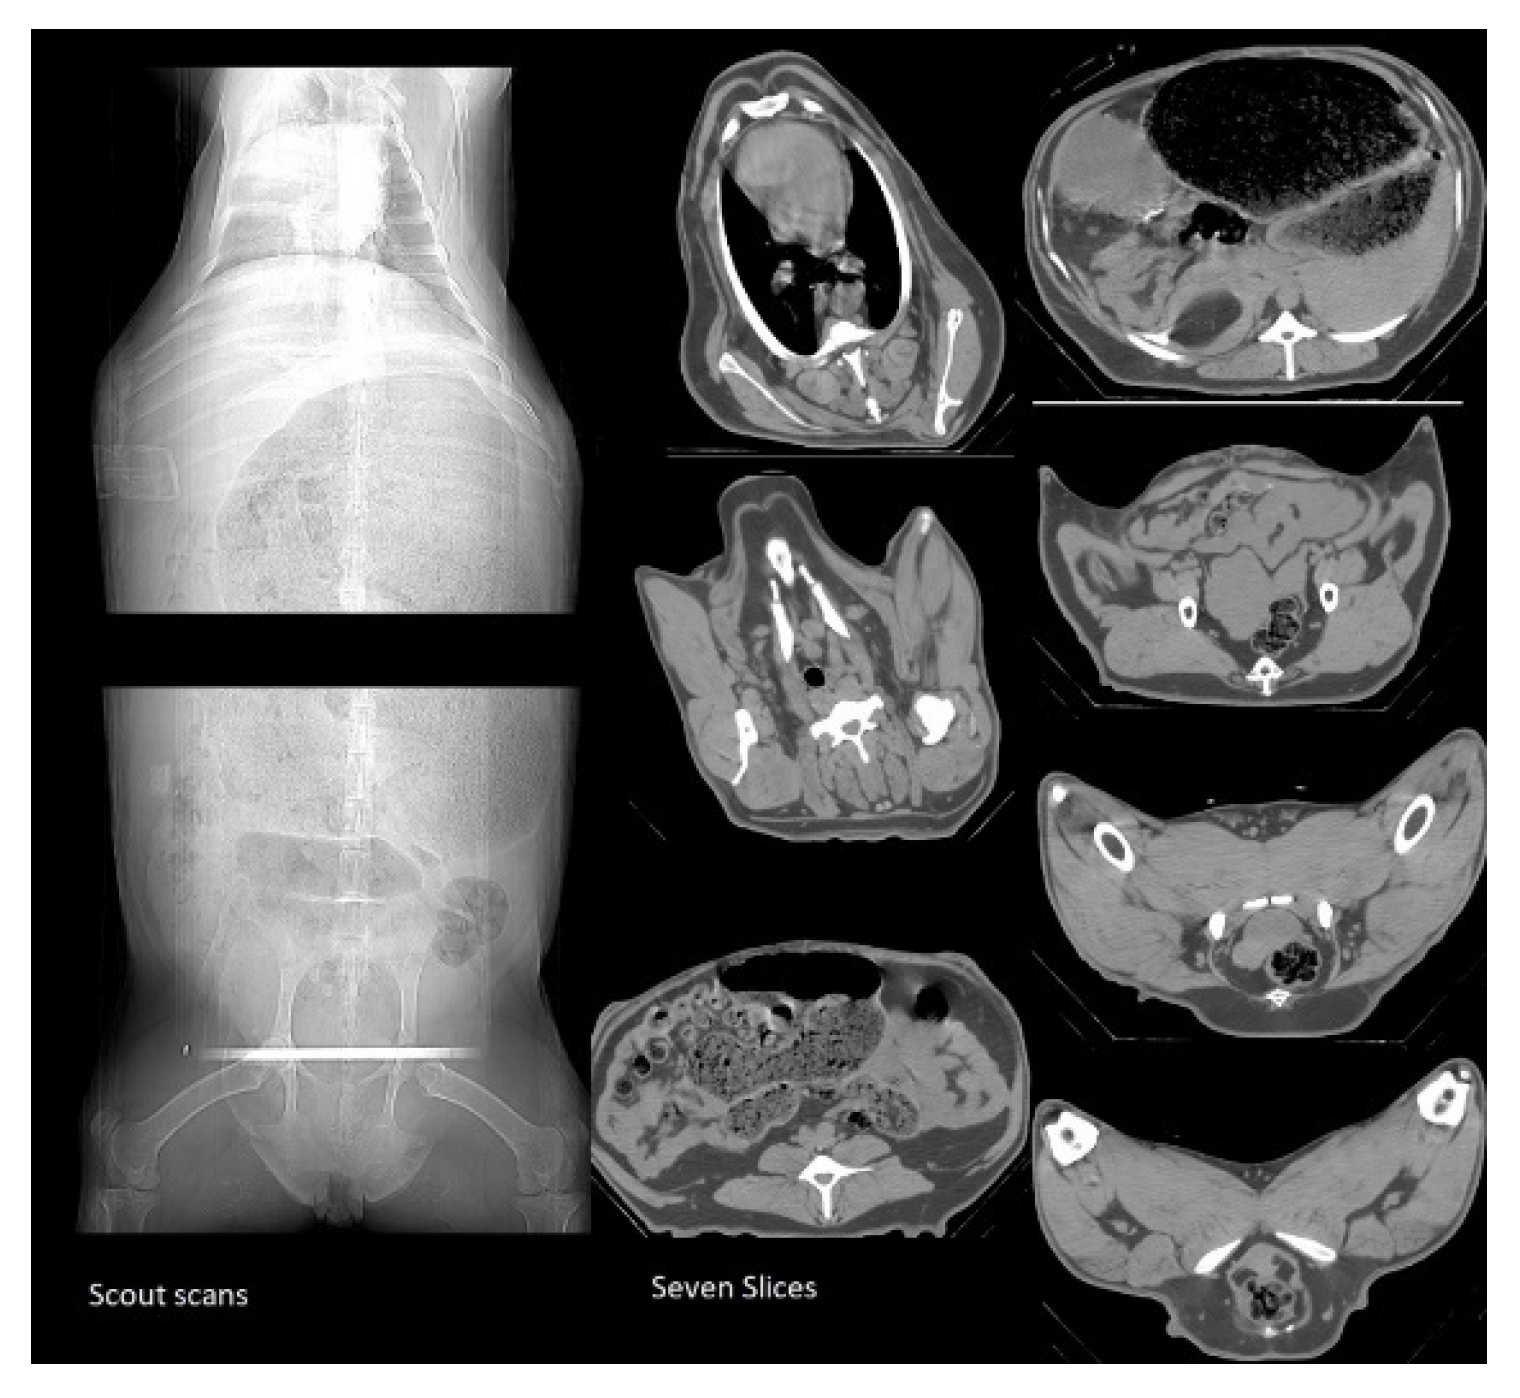

Two CT scout scans were taken for each ewe: one from the top half of the body and another from the bottom half Error! Reference source not found. The first scout scan captured three slices of the ribs. Slice 1 was taken at the first rib, slice 2 at the fifth rib and slice 3 at the last rib. The second scout scan captured four slices: one at the second to last vertebra in the spine; the second slice at the fifth rib in the middle of the pelvis; the third slice at the end of the pelvis; and the last slice was taken at the ischium. Once the scanning procedure was completed, the wooden stretcher was carried out and the ewe was released to the recovery room. The ewe was placed in the sternal recumbency recovery position and ensured that it was kept warm. Ewes were CT-scanned using a CT750 HD machine manufactured by GE Healthcare. The CT slice measurements were measured by the CT operator using the STAR 6.15 software. CT images were then analyzed by an experienced CT operator to determine the amount of fat, lean and bone for each slice based on the color (body carcass fat in dark grey areas, lean in light grey areas, bone in white and in air black areas) by drawing around these areas. These areas were measured using linear measurements or irregular drawings traced manually by the operator. The CT scanning operator held a current license to use ionizing radiation (National Radiation Laboratory) and was an accredited person (as approved for competency by the Lincoln University Animal Ethics Committee).

Figure 1. CT scout scans and the seven slices.